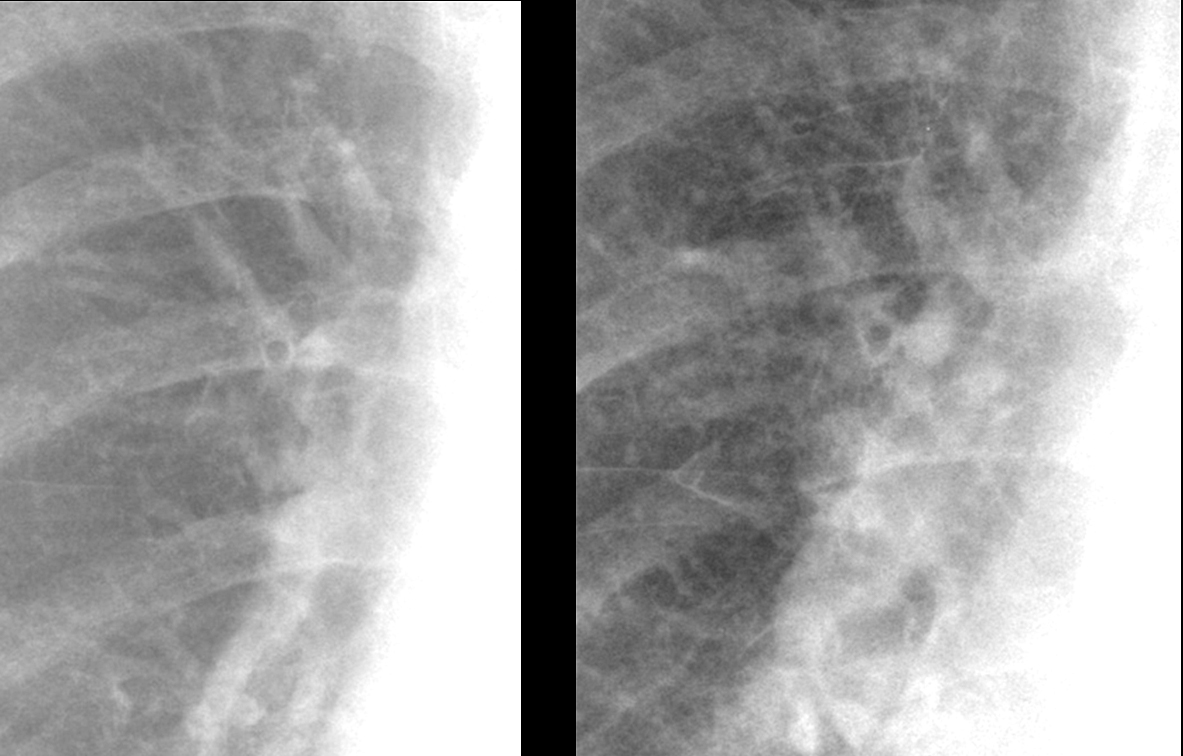

PB cuffing in failure